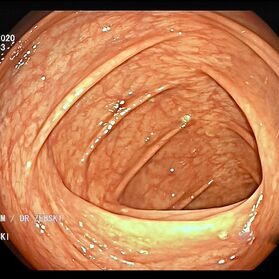

Die Darmspiegelung ist der uneingeschränkte Goldstandard für die Diagnostik und Vorsorge sämtlicher Erkrankungen des Dickdarms und des untersten Dünndarms. Die hochauflösende Bildqualität (High Definition) unserer modernen Videokoloskope ermöglicht eine zuverlässige Einordnung nahezu sämtlicher entzündlicher oder geschwulstiger Veränderungen der Dickdarmschleimhaut.

Die Darmspiegelung hilft, dass Darmkrebs gar nicht erst entstehen kann. Denn während der Untersuchung werden auch Polypen entfernt, aus denen sich der Darmkrebs in der Regel entwickelt. Von allen Maßnahmen zur Früherkennung dieser Polypen besitzt die Koloskopie die höchste Empfindlichkeit. Sie weist kleinste Polypen, aber auch Darmkrebs nach, der noch keinerlei Symptome macht. Die Abtragung dieser Polypen erfolgt direkt, wenn sie entdeckt werden. Das geschieht völlig schmerzfrei. Durch die Abtragung der Polypen kann die Entstehung von Darmkrebs effektiv verhindert und die krebsbedingte Sterblichkeit gesenkt werden.